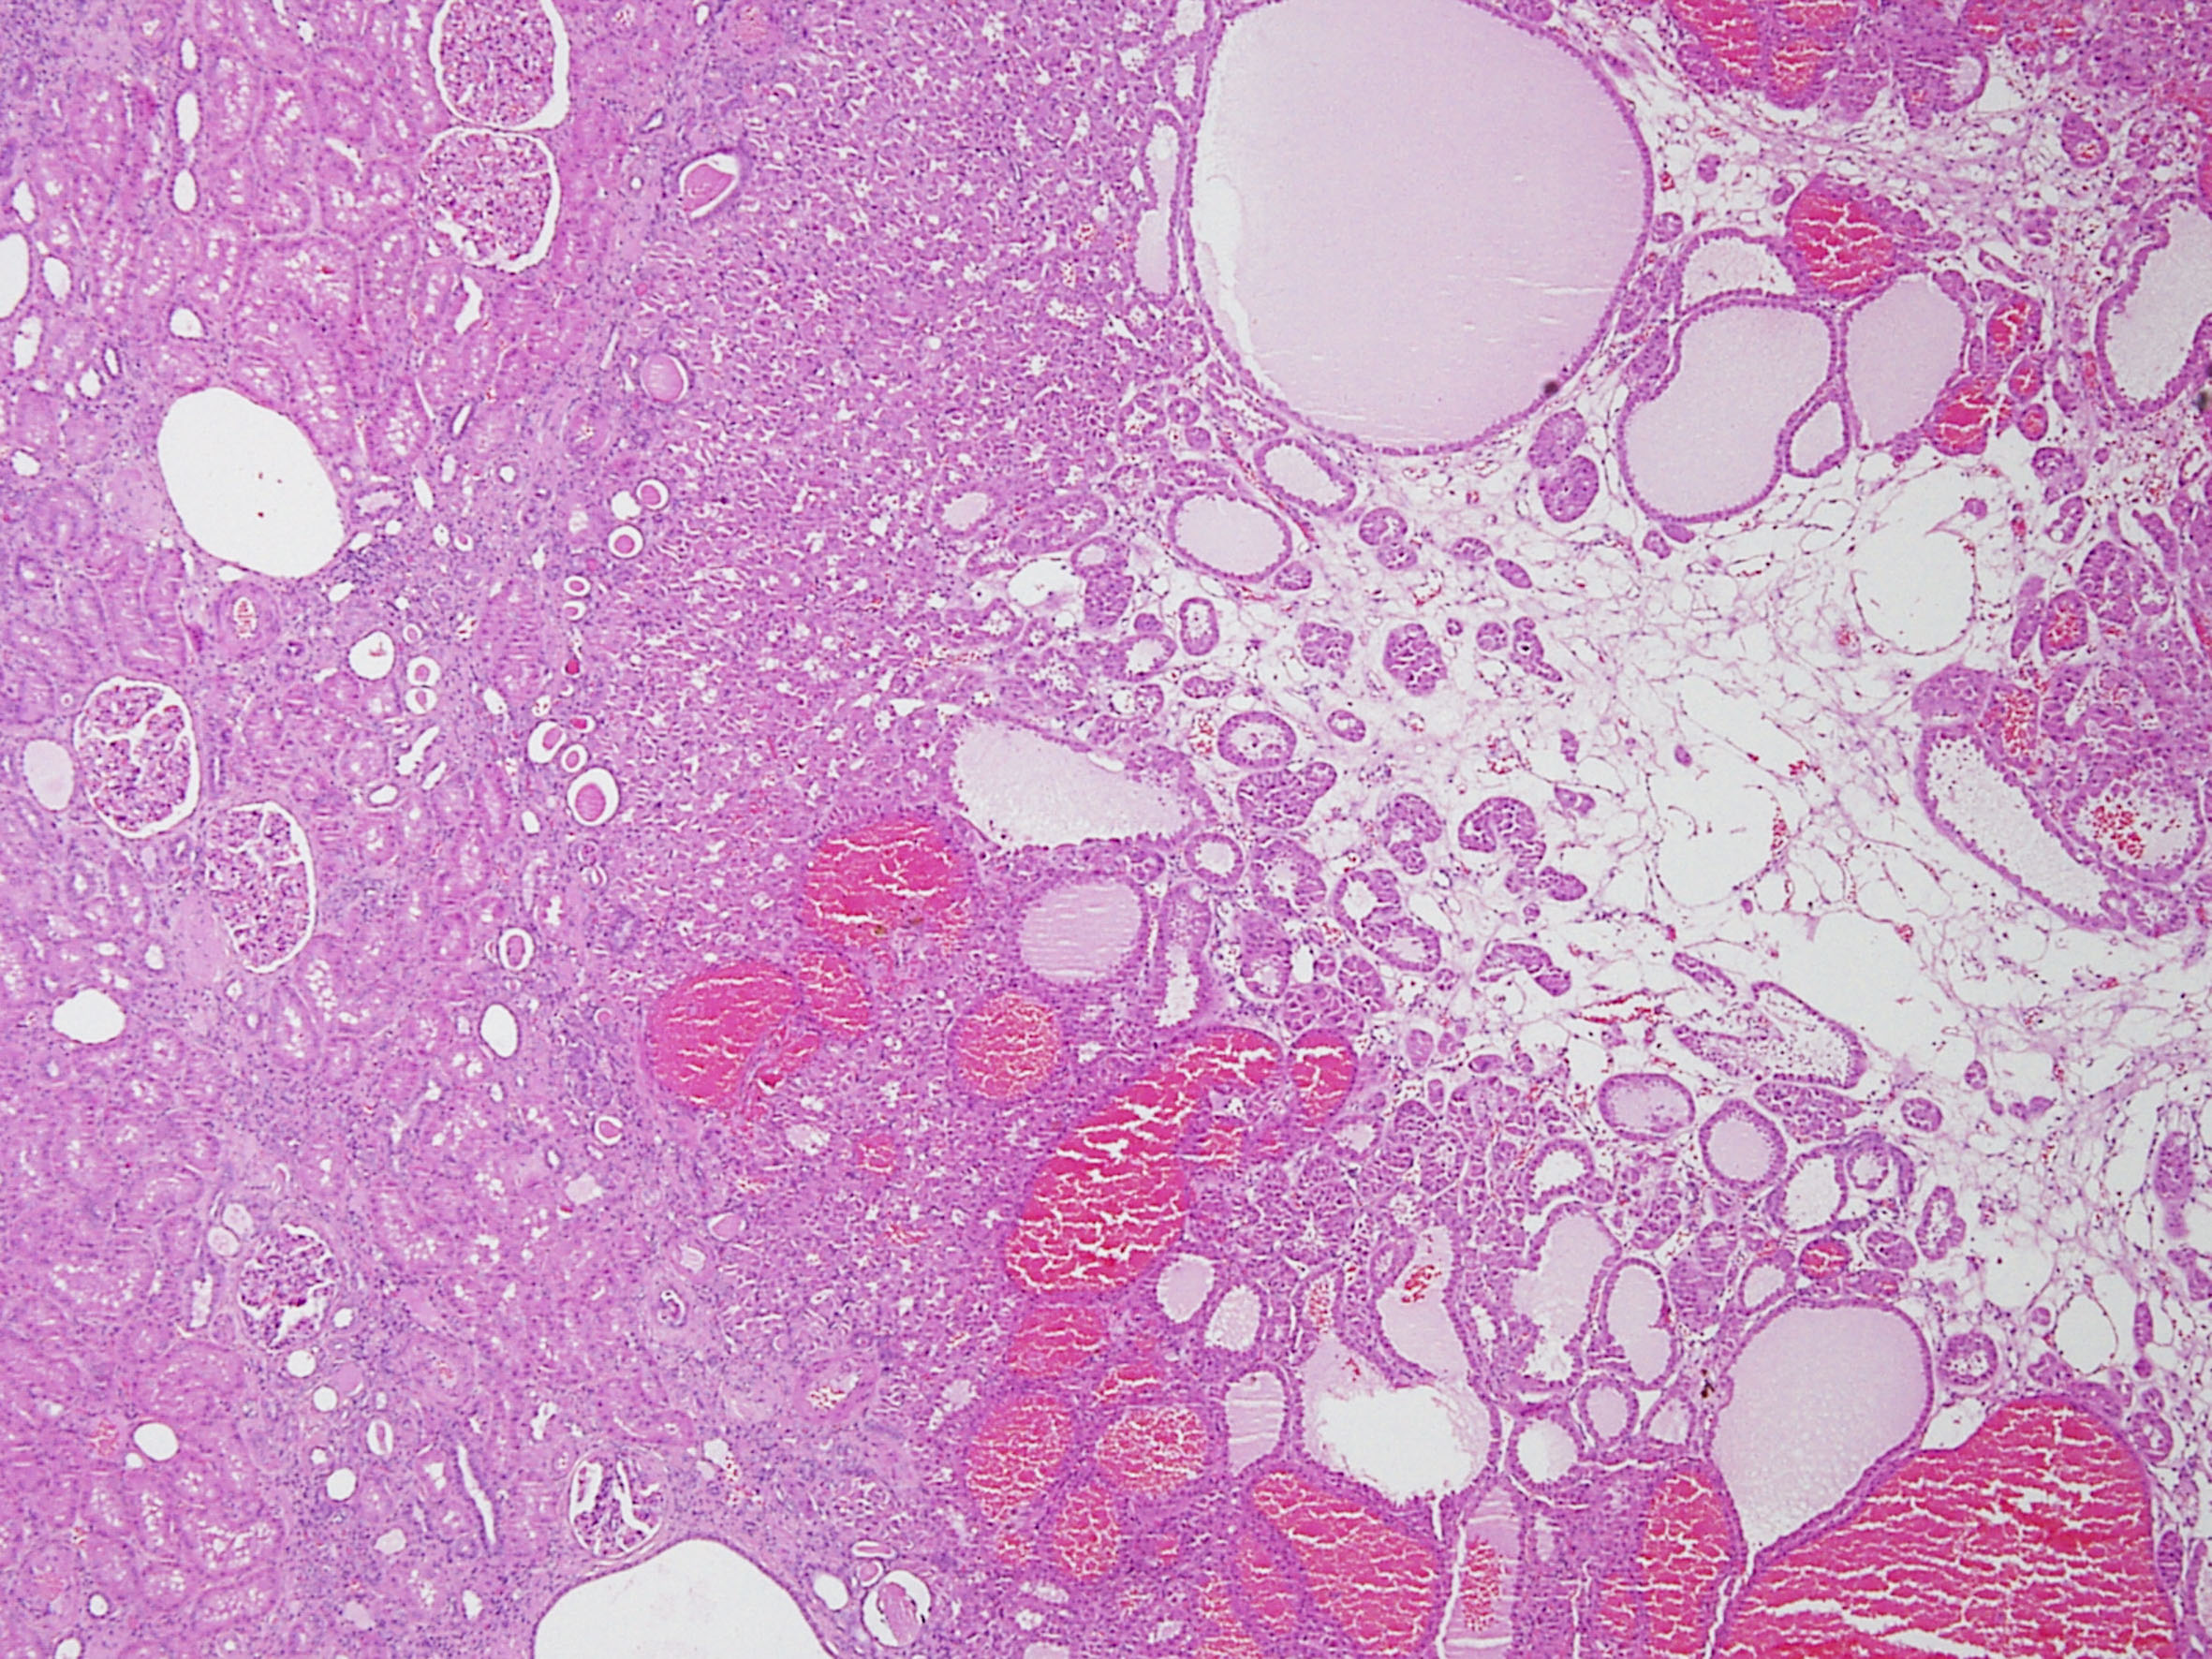

Consensus grade: oncocytoma

Case description (by case creator):

Oncocytoma